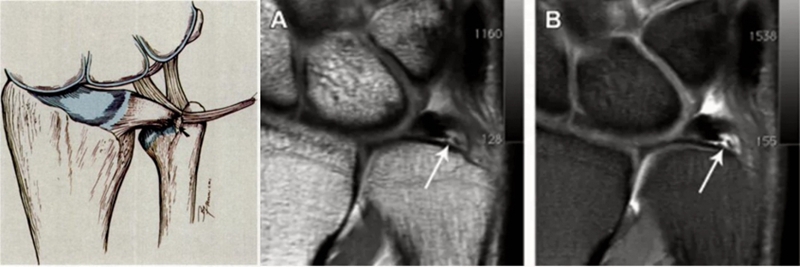

ⅠD,TFC桡侧撕裂,桡侧附着处及桡尺关节处信号增高